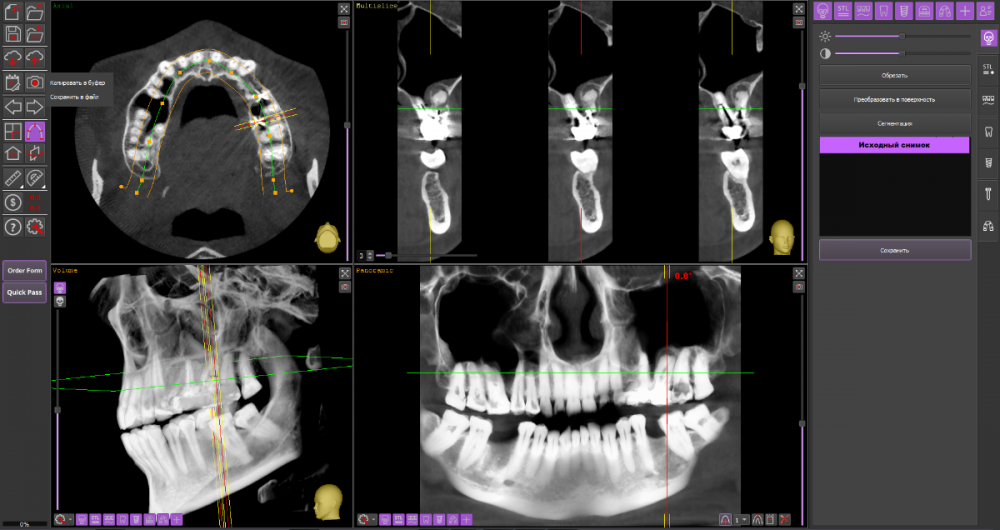

DeLaMer Опубликовано 11 августа, 2021 Поделиться Опубликовано 11 августа, 2021 (изменено) Добрый день уважаемым докторам-участникам форума. Хотелось бы, по возможности, получить экспертное мнение по поводу моей проблемы. На верхней челюсти есть мост, объединяющий 6й, 5й и отсутствующий 4 зубы (если я правильно понимаю нумерацию, это должны быть 24, 25, 26). В начале июня на десне открылся свищ с гноем (абсцесс, но, видимо, не острый, кроме периодического надувания гнойного шарика ничего больше не происходило). По этом поводу мой лечащий врач поднял КТ, которое было сделано осенью до того по другому поводу и обнаружила воспаление одного из корней 6-го зуба. При этом она высказала соображение, что может быть здесь поможет резекция верхушки того самого корня. Один из хирургов, с которым я консультировалась по этому поводу, сказал, что на его взгляд резекция возможна. Другой - что воспаление проявляется не только на одном корне, а на двух и по его мнению сделать тут ничего нельзя, только распиливать коронку и удалять 6й зуб. Я была бы крайне благодарна, если бы уважаемые специалисты высказали свое мнение по этому поводу, потому что при равноценных двух противоположных мнениях мне даже не понятно с чего начинать. Прикрепляю ссылку на файл КТ на своем дропбоксе. Огромное спасибо за помощь https://www.dropbox.com/s/fkv8cvqqq6grgpe/Sergeeva A..zip?dl=0 Изменено 11 августа, 2021 пользователем DeLaMer Ссылка на комментарий

Irouil Опубликовано 12 августа, 2021 Поделиться Опубликовано 12 августа, 2021 По представленным средам создаётся впечатление, что у зуба фактически разрушено соединение между корнями. Риски того, что он под нагрузкой раскроется в любой момент, достаточно высоки Ссылка на комментарий

АнтонТЛТ Опубликовано 13 августа, 2021 Поделиться Опубликовано 13 августа, 2021 (изменено) Там всё ок с фуркацией и вкладка коротконогая. Просто на КТ очень много артефактов. Изменено 13 августа, 2021 пользователем АнтонТЛТ Ссылка на комментарий